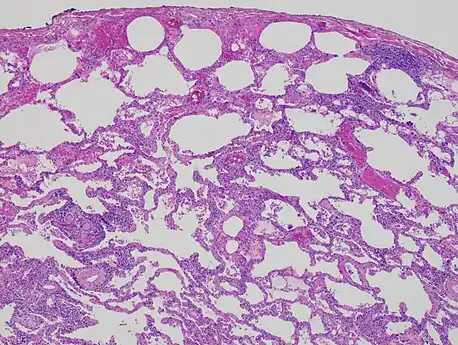

Low magnification view of the histology of chronic hypersensitivity pneumonitis. The interstitium is expanded by a chronic inflammatory infiltrate. Two multinucleated giant cells can be seen within the interstitium at left, and a plug of organizing pneumonia at bottom left. -

Lung biopsy

Lung biopsies can be diagnostic in cases of chronic hypersensitivity pneumonitis, or may help to suggest the diagnosis and trigger or intensify the search for an allergen. The main feature of chronic hypersensitivity pneumonitis on lung biopsies is expansion of the interstitium by lymphocytes accompanied by an occasional multinucleated giant cell or loose granuloma.[17][24]

When fibrosis develops in chronic hypersensitivity pneumonitis, the differential diagnosis in lung biopsies includes the idiopathic interstitial pneumonias.[25] This group of diseases includes usual interstitial pneumonia, non-specific interstitial pneumonia and cryptogenic organizing pneumonia, among others.[17][24]

The prognosis of some idiopathic interstitial pneumonias, e.g. idiopathic usual interstitial pneumonia (i.e. idiopathic pulmonary fibrosis), are very poor and the treatments of little help. This contrasts the prognosis (and treatment) for hypersensitivity pneumonitis, which is generally fairly good if the allergen is identified and exposures to it significantly reduced or eliminated. Thus, a lung biopsy, in some cases, may make a decisive difference.